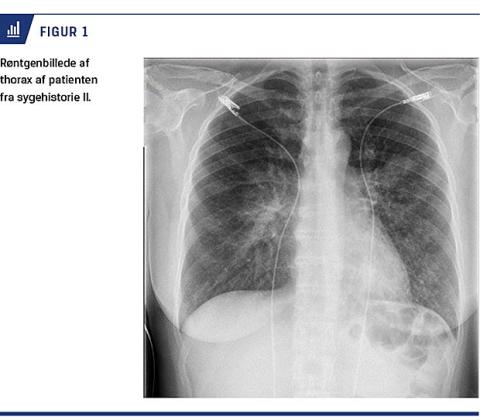

II. En 47-årig tidligere rask kvinde blev indlagt på en infektionsmedicinsk afdeling. Hun var svært dyspnøisk og febril efter seks dages influenzalignende symptomer uden effekt af en penicillinkur. Paraklinisk blev der målt følgende værdier: leukocytter 9,8 mia./l og CRP: 195. Der var normale værdier for hæmoglobin og P-bilirubin. En røntgenundersøgelse af thorax (Figur 1) viste infiltrater bilateralt, og hun blev sat i behandling med penicillin og clarithromycin givet i.v. Penicillinen blev

seponeret, efter at der var en positiv PCR-reaktion for M. pneumoniae. Pga. manglende effekt på dag fem tillagde man ciprofloxacin for at undgå evt. makrolidresistens. På dag seks faldt hæmoglobinniveauet til 3,2 mmol/l og P-haptoglobinniveauet til 0,08 g/l. P-bilirubinniveauet steg til 78 mikromol/l og retikulocytniveauet til 29 mia./l. På mistanke om kuldeagglutininudløst autoimmun hæmolytisk anæmi, kom patienten i behandling med prednisolon og blev optransfunderet med opvarmet blod. Dagen efter blev blodprøverne testet DAT-positive for antiC3d og negative for anti-IgG. Der blev desuden målt et kuldeagglutininniveau på 256. På dag otte fik patienten knugende brystsmerter og blev overflyttet til kardiologisk regi, hvor man diagnosticerede et iskæmiudløst type 2-akut myokardieinfarkt uden sequelae. Derefter aftog hæmolysen hurtigt, og på dag 15 kunne hun udskrives til ambulant kontrol. Ciprofloxacin blev seponeret på dag 14 og clarithromycin på dag 22. På dag 26 tog man en ny ekspektoratprøve, som viste makrolidresistente M. pneumoniae-bakterier.